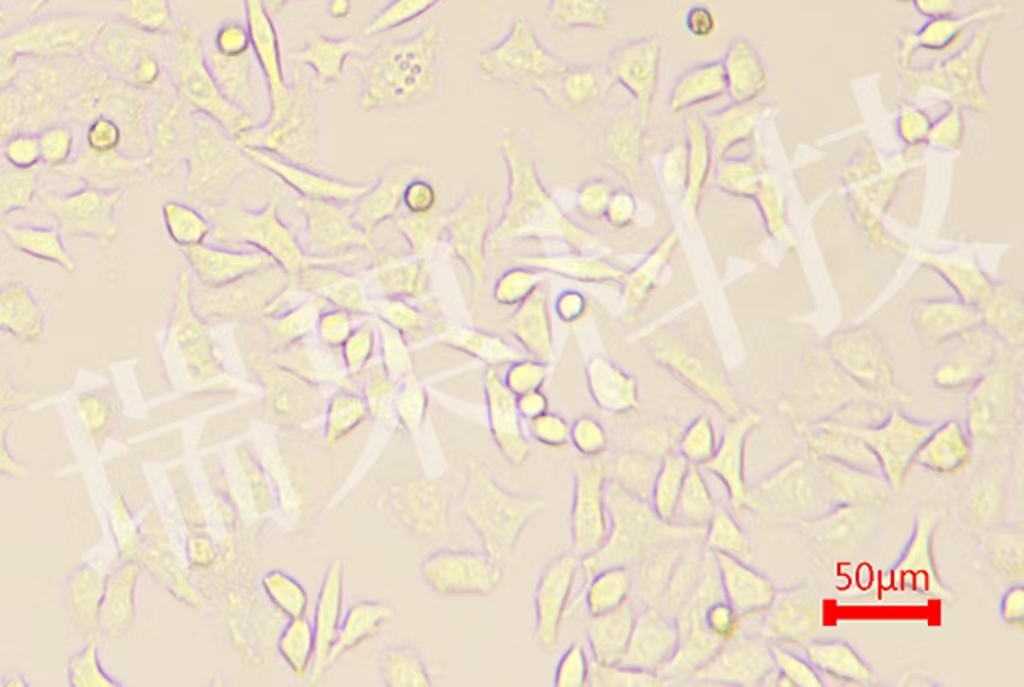

阿辛蓝染色:细胞化学染色是形态学与化学或生物化学相结合的一种检查技术。临床采用阿利新蓝染色法进一步鉴别各类血细胞提高对急性早幼粒细胞白血病诊断具有重要意义。

阿辛蓝染色:细胞化学染色是形态学与化学或生物化学相结合的一种检查技术。临床采用阿利新蓝染色法进一步鉴别各类血细胞提高对急性早幼粒细胞白血病诊断具有重要意义